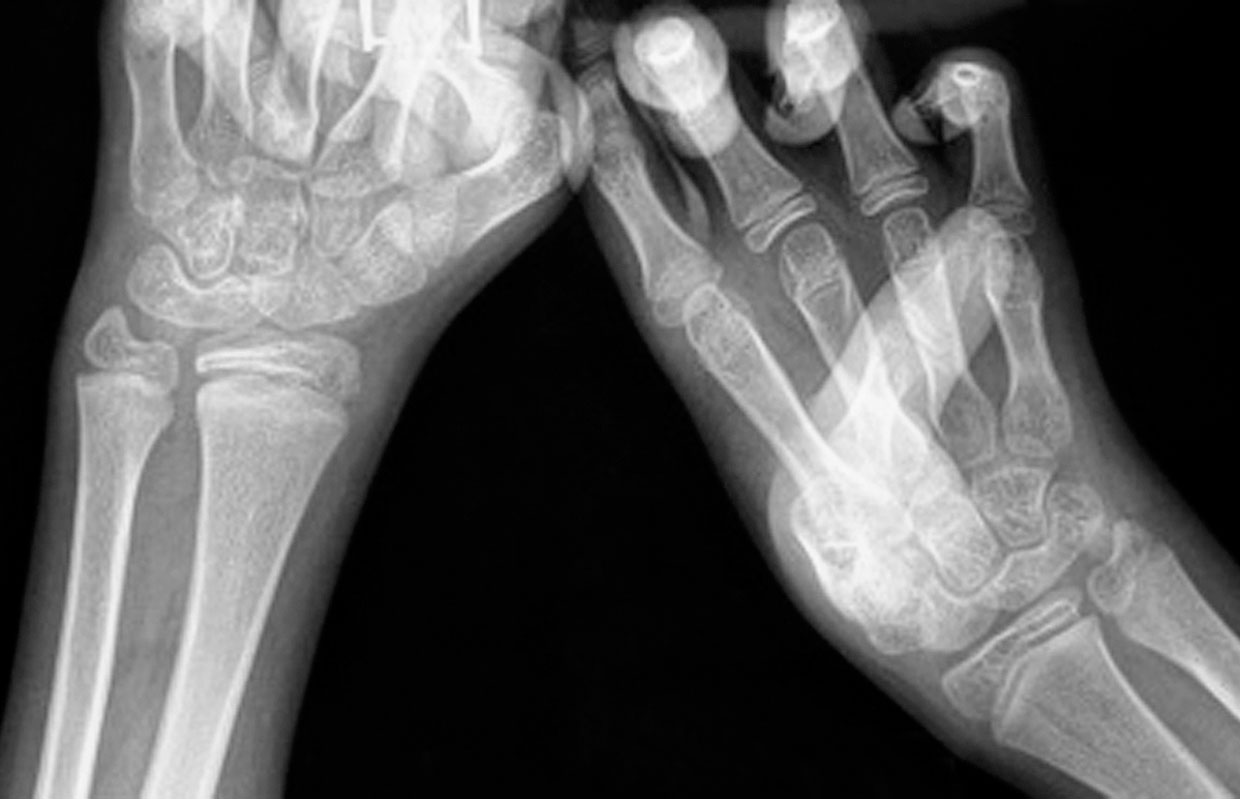

A.左侧前臂尺侧纵列发育不良;B.X 线片显示左侧肱骨桡尺骨融合(全肘关节融合),合并尺骨发育不良(尺骨远端部分缺如),桡骨继发性侧弯,第Ⅰ、Ⅱ及第Ⅳ、Ⅴ掌骨融合